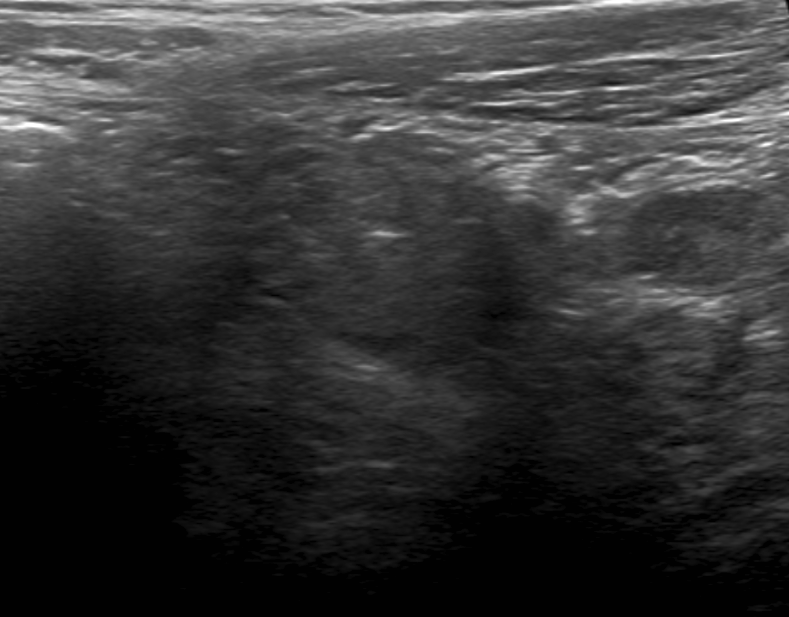

Ultrasound is a fast and cost effective option for analysis of potential appendicitis. It can be performed at the bedside if necessary, and no radiation is involved.

Pertinent Imaging Observations

Click on the links below to view images from the study, and assess these key findings as best you can.

Because of gas obscuring the appendix on ultrasound, a CT is required to assess this case. A CT with contrast is preferred where possible. It will help with assessment of an inflamed appendix.

Socioeconomic Factors: The diagnosis of appendicitis can often be made by ultrasound, especially in the pediatric population. It would be lower cost and there is no radiation exposure. However, the appendix may be obscured by bowel gas and a CT would be necessary if clinical suspicion remains high.